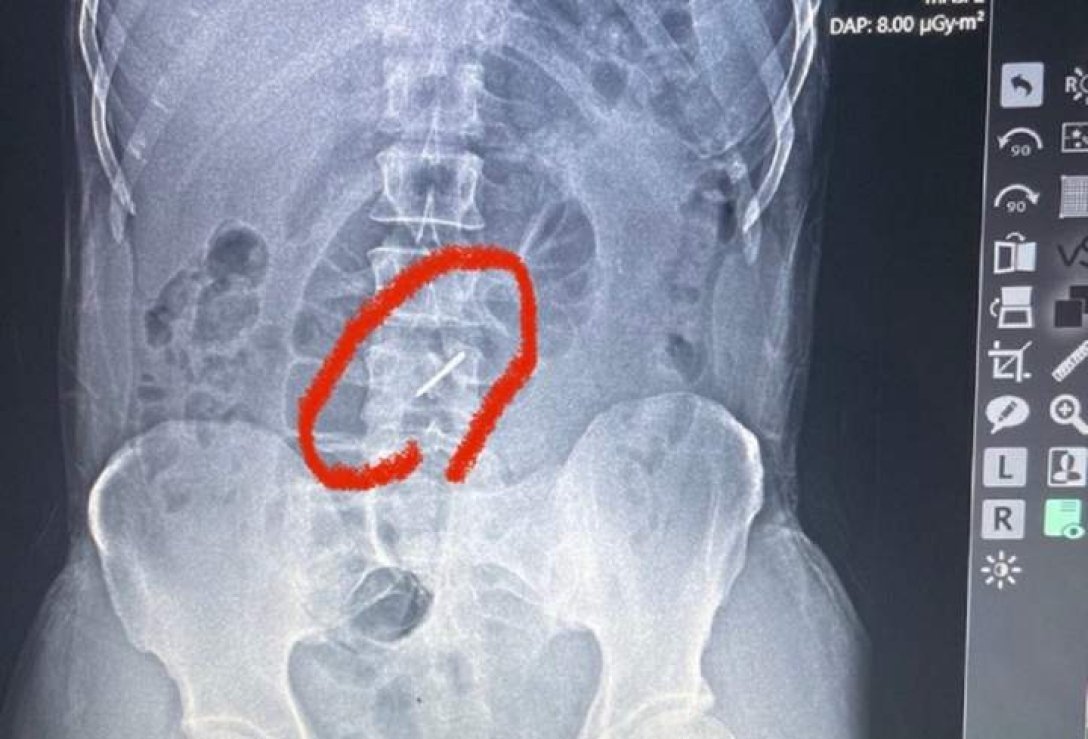

"Стрілка" від касетного боєприпасу зламала 44-річному бійцю два поперекові хребці та застрягла в хребті. Але військовий звернувся до медиків через високу температуру.

Як розповідають журналісти, під час одного з обстрілів "стрілка" від касетного боєприпасу зламала чоловікові два поперекові хребці та застрягла у хребті. Однак боєць (ім'я якого не називають з метою безпеки) не помітив цього. До шпиталю він звернувся лише тоді, коли біль у попереку почав справді йому заважати, а температура піднялася до 39 градусів. Медикам чоловік сказав, що в нього, мабуть, радикуліт.

За словами лікаря військово-польового шпиталю, львівського судинного хірурга Тараса Кобзи, військового відправили на рентген, після чого й з'ясувалась причина його болю у попереку.

"Під час обстрілу елемент касетної бомби потрапив у ліве підребер'я, зламав два хребці в поперековому відділі та застряг у хребті", — пояснив лікар.

"Стрілку" касетного боєприпасу медики помітили вже під час рентгену

Як каже Кобза, уламки зламаних хребців могли пошкодити нерви та судини, але, на щастя, цього не сталося. Сам чоловік підкреслив, що навіть не підозрював про "стрілку", яка застрягла у хребті.

У цьому випадку "стрілка" потрапила бійцю в підребер'я, де він має кілька родимок. Прокол шкіри виявився всього приблизно 1 мм, тому військовий його навіть не помітив, подумав, що це лише одна з родимок.